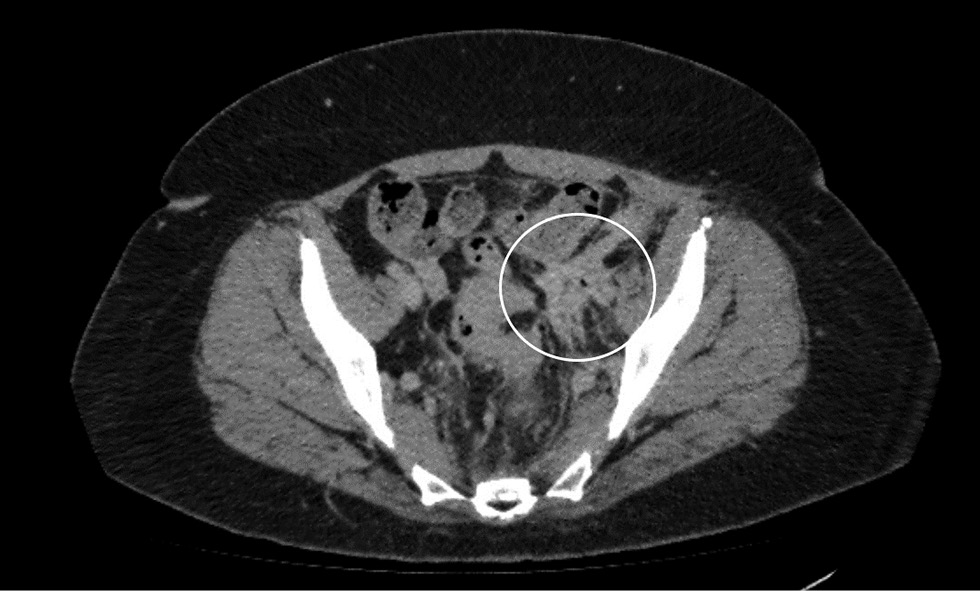

Рис. 4. Компьютерная томография органов брюшной полости. Стрелкой отмечена пиелэктоазия слева

Fig. 4. Computed tomography of the abdomen. The arrow indicates pyelectasis on the left

По данным контрольной КТ от 17.03.2022: в левой половине малого таза над мочевым пузырем определяется конгломерат петель кишки, заполненный содержимым, не отделимый от стенки мочевого пузыря, утолщенной и накапливающей рентгенконтрастный препарат. В просвете мочевого пузыря обнаружен воздух (рис. 2.). Отмечен отек внутритазовой клетчатки, расширение тазовых сплетений слева. Дистальный отдел левого мочеточника теряется в инфильтрате, присутствует умеренная левосторонняя пиелоуретероэктазия (рис. 3, 4).